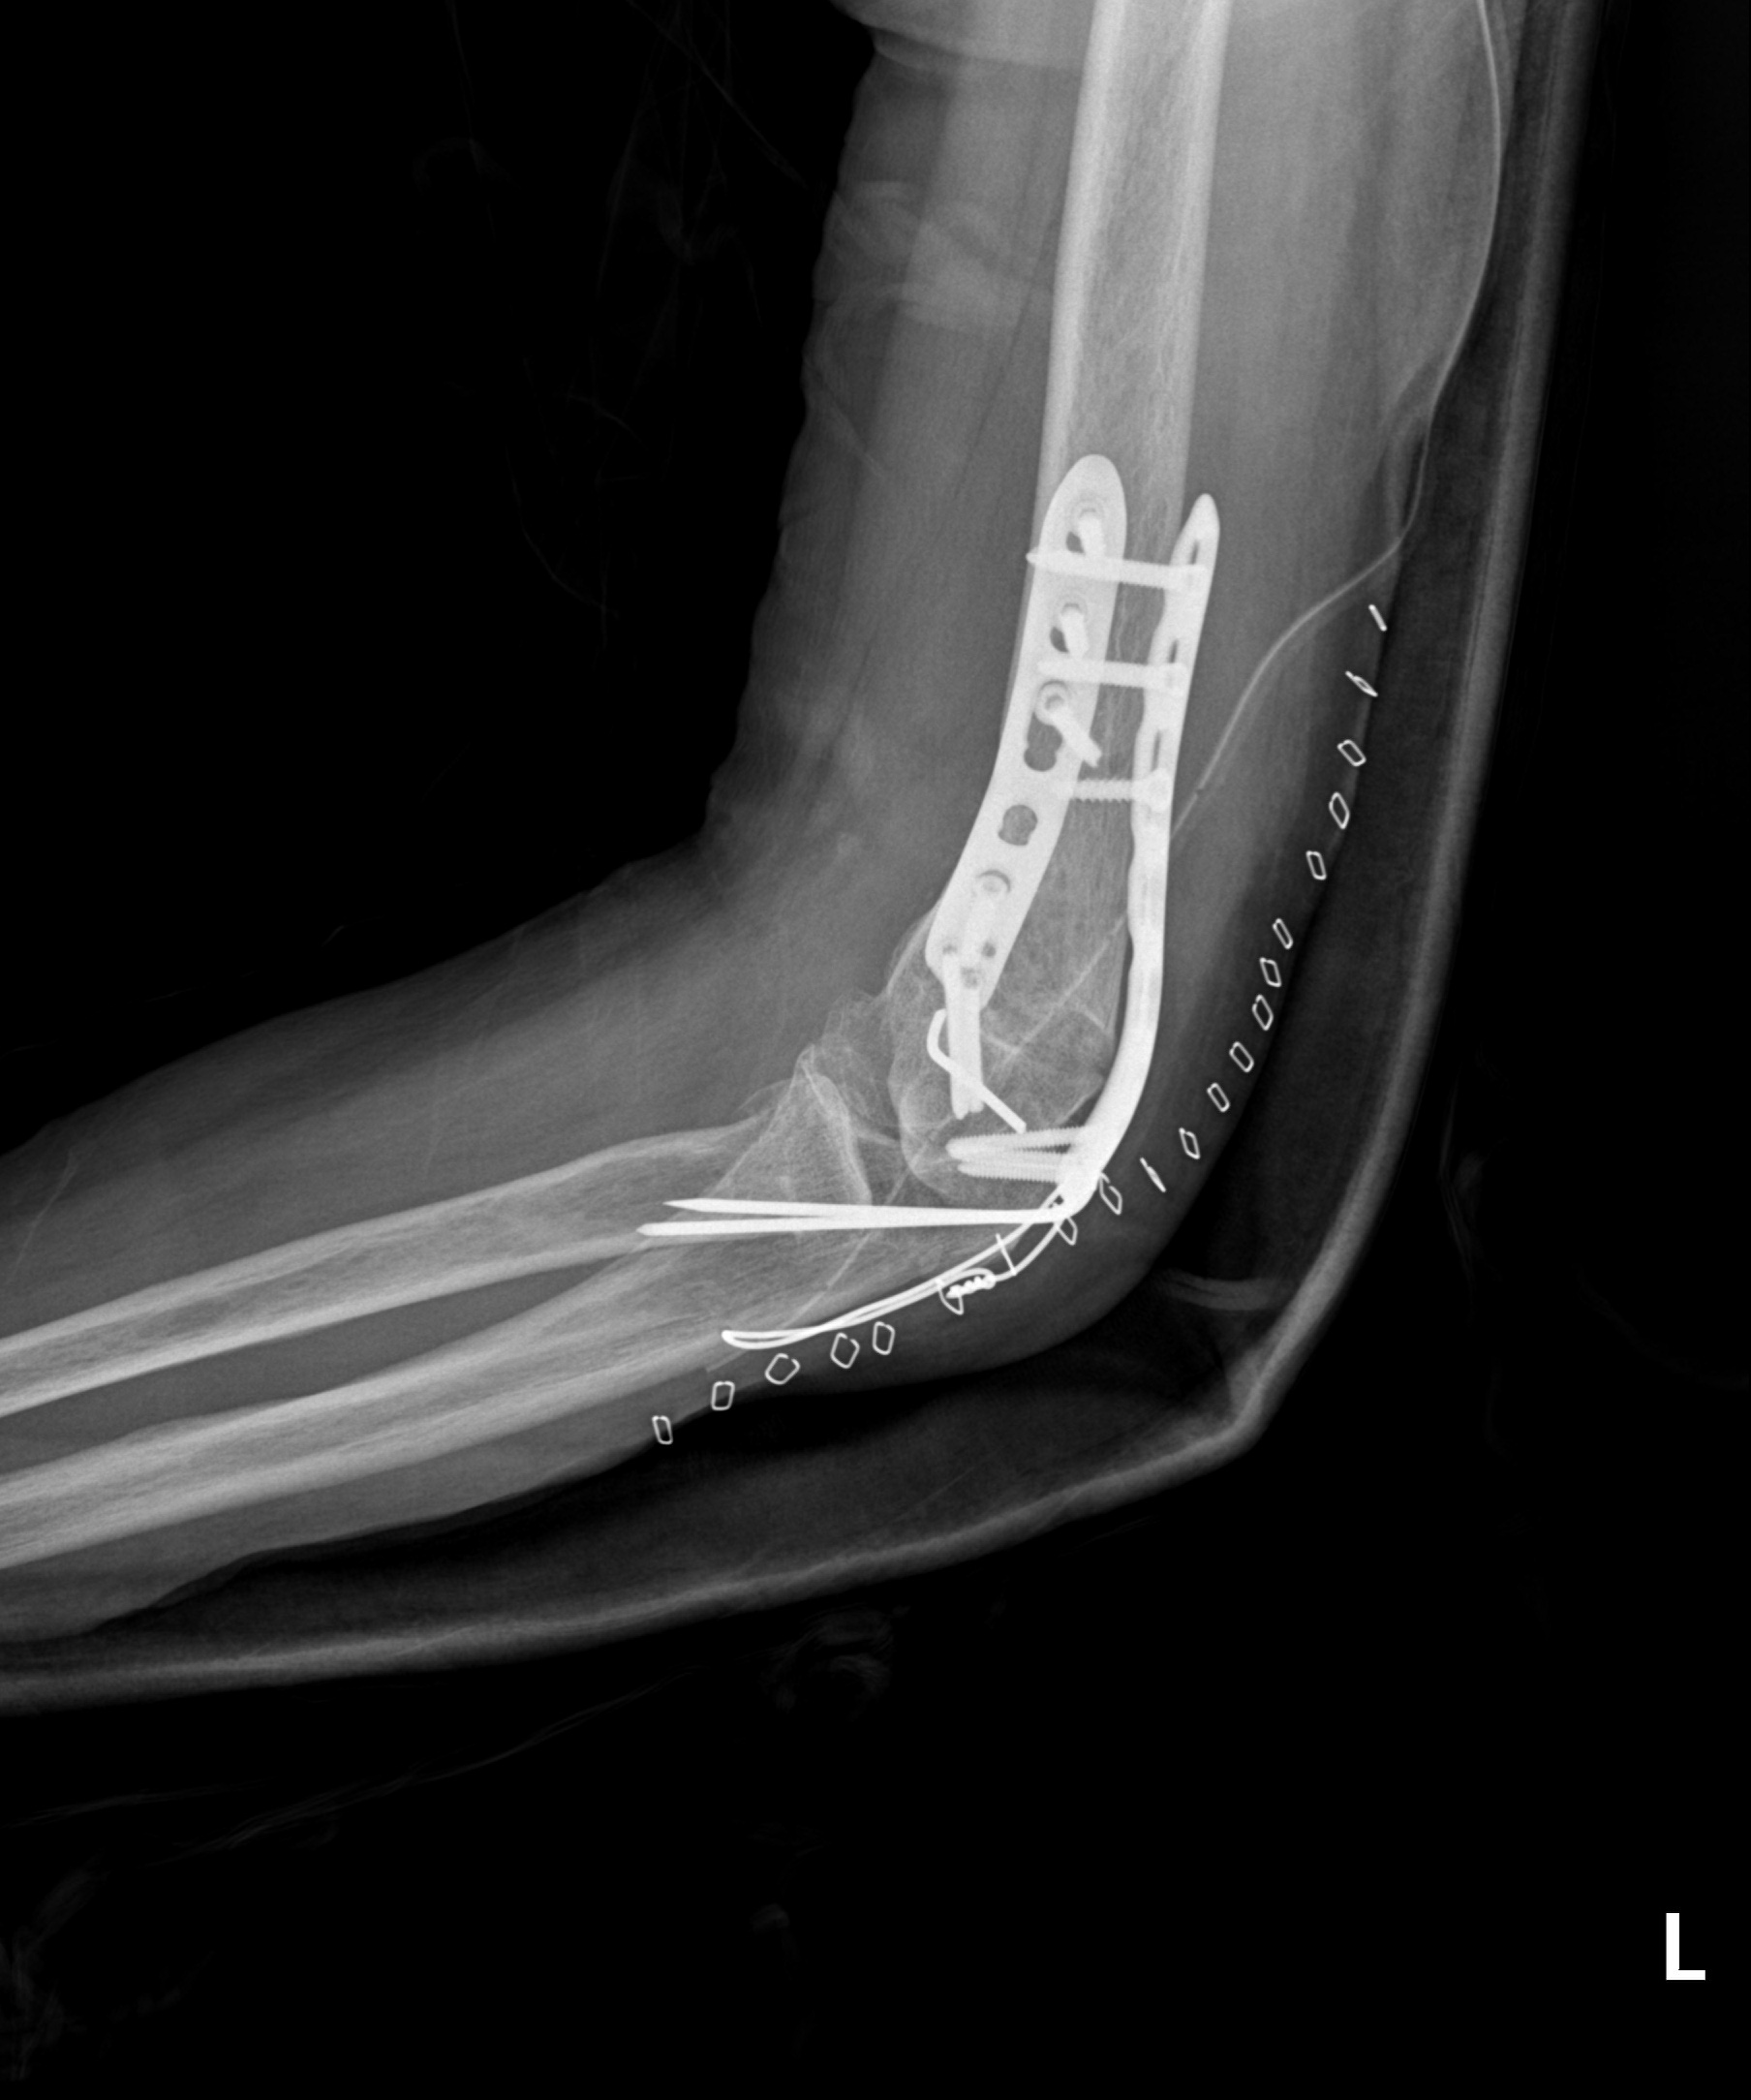

원위 상완골 골절

2022.07.14

2023.02.07